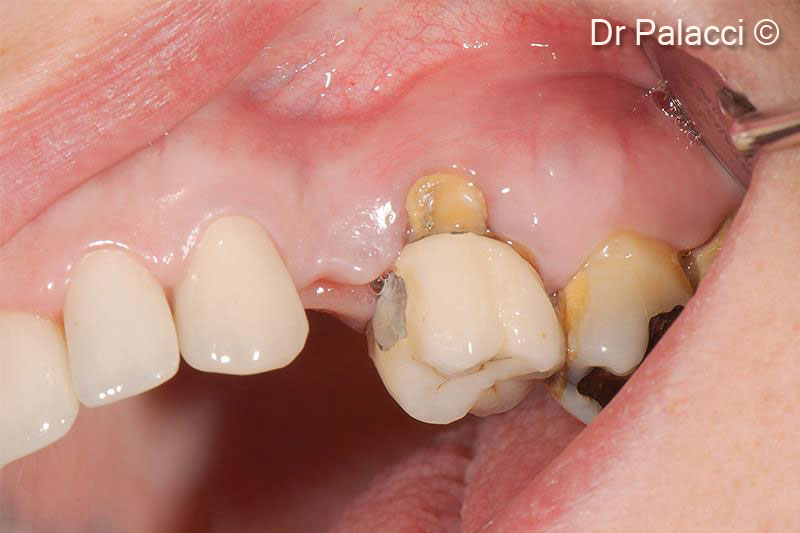

Hình thái khuyết hổng xương có sự khác biệt giữa các bệnh nhân. GTO® là vật liệu ghép dị loại dạng Sticky bone hai pha (Dual-Phase), được đặc trưng bởi khả năng thích ứng cao với vị trí tiếp nhận và độ ổn định vượt trội sau khi ghép. GTO® cho phép hình thành xương mới đầy đủ⁽¹–⁴⁾ và bảo tồn thể tích ổ răng khi được sử dụng trong GBR⁽⁵⁾ tại các ổ răng sau nhổ có kế hoạch cấy ghép trì hoãn, kể cả trong những trường hợp ổ răng sau nhổ bị tổn thương. Khi kết hợp với Lamina® , GTO® cũng là lựa chọn phù hợp trong điều trị các khuyết xương theo chiều ngang⁽¹⁾ (ví dụ: mào xương dạng lưỡi dao – knife-edge ridge).Nhờ tính bám dính và khả năng thao tác dễ dàng, GTO® có thể được sử dụng để tái tạo xương quanh các khiếm khuyết dạng hở quanh implant (peri-implant dehiscence)⁽⁵⁾ .